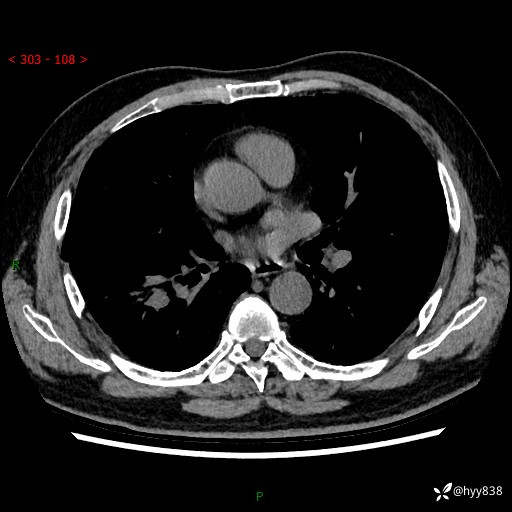

【现病史】:患者半月前无明显诱因出现咳嗽、咳痰,为白色粘痰,无明显加重与缓解因素,伴气促,无发热,无大量脓痰,无胸痛、咯血,无哮鸣音,到我院就诊,胸部CT示右肺结节增大,并口服药物治疗无明显好转,具体用药不详,为求进一步治疗随来我院,经门诊以“孤立性肺结节”收入我科。 病程中患者精神、饮食可,睡眠不佳,大小便正常,体力下降,体重未见明显下降。

【检查】:胸部CT平扫+增强